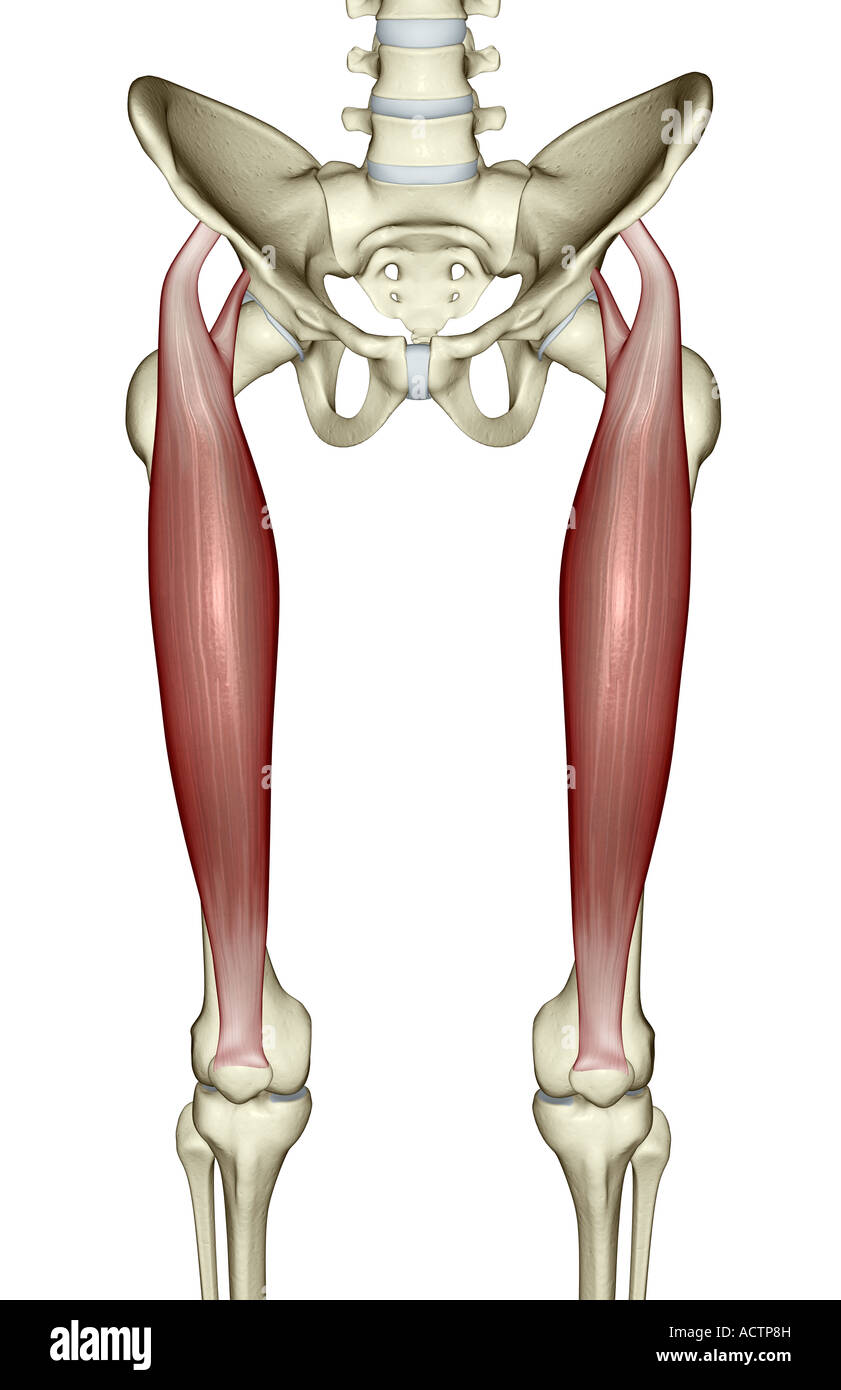

Rectus femoris Banque D'Imageshttps://www.alamyimages.fr/image-license-details/?v=1https://www.alamyimages.fr/photo-image-rectus-femoris-13228864.html

Rectus femoris Banque D'Imageshttps://www.alamyimages.fr/image-license-details/?v=1https://www.alamyimages.fr/photo-image-rectus-femoris-13228864.htmlRFACTP8H–Rectus femoris